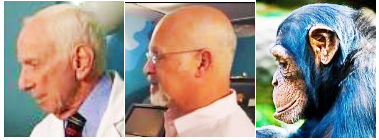

Treatment traditionally has consisted of performing a myringotomy,

making a small cut in the eardrum (tympanic membrane), followed by

flushing the middle ear to force out the mucus plug. (See photo at

right.) Topical and/or

systemic corticosteroids and antibiotics then are administered. The

procedure may have to be repeated, in some cases several times,

depending upon how the dog responds. An alternative procedure is a

Treatment traditionally has consisted of performing a myringotomy,

making a small cut in the eardrum (tympanic membrane), followed by

flushing the middle ear to force out the mucus plug. (See photo at

right.) Topical and/or

systemic corticosteroids and antibiotics then are administered. The

procedure may have to be repeated, in some cases several times,

depending upon how the dog responds. An alternative procedure is a

• myringotomy

Treatment

primarily has consisted of performing a myringotomy

(see photo at right), making a small cut in the eardrum (tympanic

membrane), followed by flushing the middle ear to force out the mucus

plug. The photograph at right is of a myringotomy in progress. The ring

in the middle of the photo is the eardrum. The tube tip at the top is

the device used to flush the inner ear and force out the mucus. You may

watch a

In a

March 2008 study conducted

by Australian researchers, they inserted tympanostomy tubes

(TT)

(right) within the

myringotomy incision in order to provide continual tympanic cavity

ventilation and drainage. They found that in the cases of the three

CKCSs which they operated on, all three dogs were asymptomatic at the

time of follow-up, 8, 6 and 4 months later, and they concluded that the

use of tympanostomy tubes may be an acceptable alternative to repeated